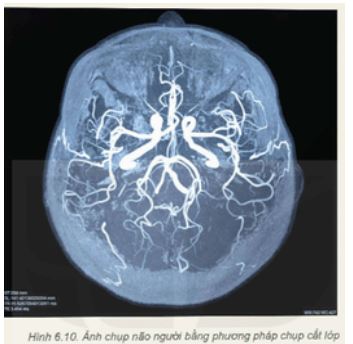

Giải thích lí do tại sao khi chụp não thì chụp cắt lớp lại thích hợp hơn X-quang (Hình 6.10).

Lời giải:

Khi chụp não thì chụp cắt lớp lại thích hợp hơn X-quang vì:

- Hình ảnh chụp được rõ nét

- Độ phân giải hình ảnh mô mềm cao hơn nhiều so với chụp X quang;

- Thời gian chụp nhanh, nhất là khi cần khảo sát và đánh giá bệnh nhân phải cấp cứu;

- Độ phân giải không gian cao;

- Các tế bào não, noron thần tinh có số lượng rất lớn nên cần phải có kết quả chụp rõ nét nhất có thể.

- Chụp được nhiều góc chụp và cho nhiều lát cắt, tránh bỏ sót tổn thương;